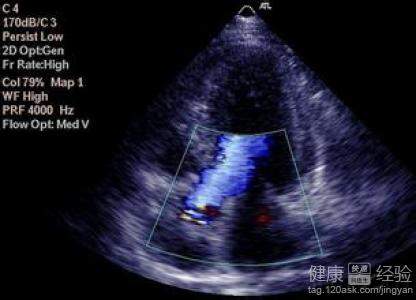

1該病的發生主要是由於化妝的心室雙側已經出現了明顯的擴大跡象,這時候就很容易導致患者的心室收縮功能減退,伴或不伴充血性心力衰竭,室性或房性心律失常多見。病情呈進行性加重,死亡可發生於疾病的任何階段。